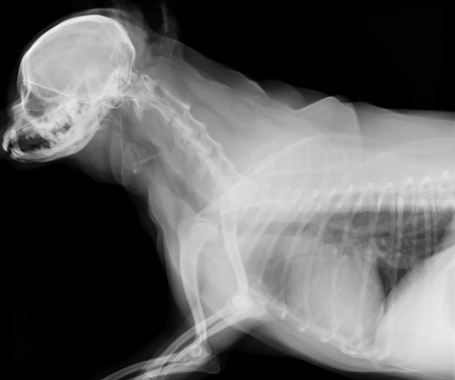

先ほどのコイルを気管に巻き付け、細かく縫合していきます。

気管を拡張するように縫合し、気管が広くなっているのが確認できました。